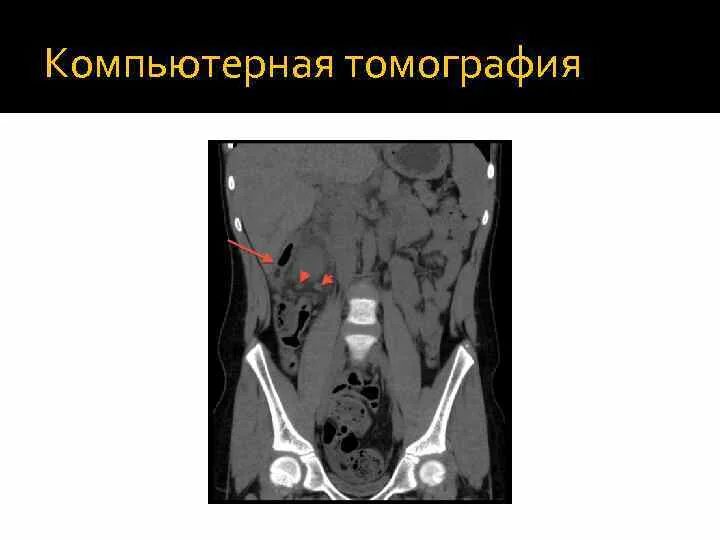

Абсцесс при аппендиците